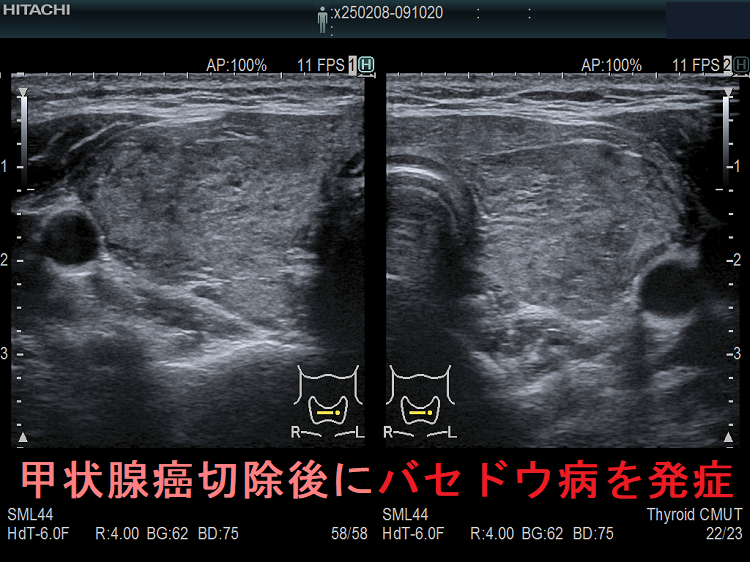

長崎甲状腺クリニック(大阪)で採用している抗甲状腺薬の中止基準(抗甲状腺薬の中止基準)・アイソトープ(放射性ヨウ素)治療・手術療法での再発はありません(ただし、中途半端な甲状腺亜全摘術を除く)。

一般的な抗甲状腺薬の中止基準を用いてバセドウ病治療を中止後、再度甲状腺ホルモンが上昇して来たら、78%はバセドウ病の再発ですが、22%は一時的な甲状腺の破壊による無痛性甲状腺炎です(「上條甲状腺クリニックの甲状腺疾患Q&A」より)。

上條甲状腺クリニックの統計によると、バセドウ病/甲状腺機能亢進症の再発は、

- 1年以内再発62%

- 2年以内再発85%

- 3年以内再発92%

で、結局ほとんどが再発し、よくこんな中止基準を作ったものだと思います。